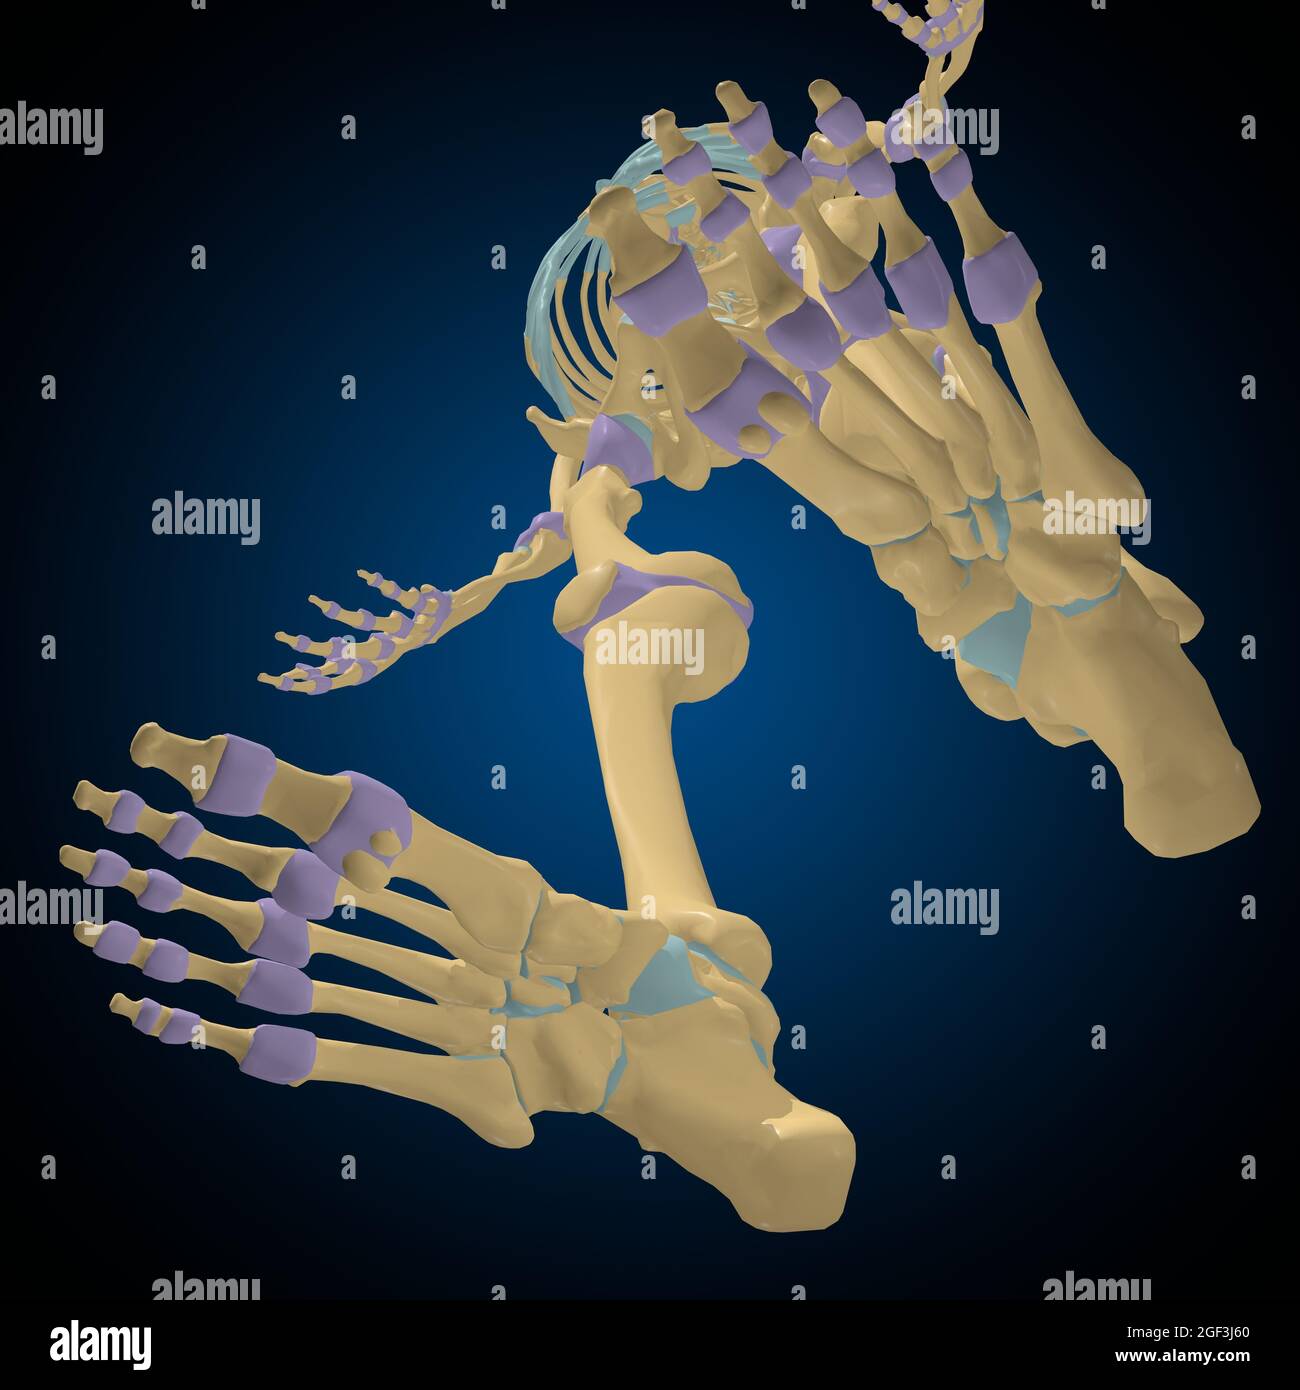

Articular capsule Anatomy For Medical Concept 3D Illustration Stock Photohttps://www.alamy.com/image-license-details/?v=1https://www.alamy.com/articular-capsule-anatomy-for-medical-concept-3d-illustration-image439559253.html

Articular capsule Anatomy For Medical Concept 3D Illustration Stock Photohttps://www.alamy.com/image-license-details/?v=1https://www.alamy.com/articular-capsule-anatomy-for-medical-concept-3d-illustration-image439559253.htmlRF2GF3J8N–Articular capsule Anatomy For Medical Concept 3D Illustration

Articular capsule Anatomy For Medical Concept 3D Illustration Stock Photohttps://www.alamy.com/image-license-details/?v=1https://www.alamy.com/articular-capsule-anatomy-for-medical-concept-3d-illustration-image439559233.html

Articular capsule Anatomy For Medical Concept 3D Illustration Stock Photohttps://www.alamy.com/image-license-details/?v=1https://www.alamy.com/articular-capsule-anatomy-for-medical-concept-3d-illustration-image439559233.htmlRF2GF3J81–Articular capsule Anatomy For Medical Concept 3D Illustration

Articular capsule Anatomy For Medical Concept 3D Illustration Stock Photohttps://www.alamy.com/image-license-details/?v=1https://www.alamy.com/articular-capsule-anatomy-for-medical-concept-3d-illustration-image439559176.html

Articular capsule Anatomy For Medical Concept 3D Illustration Stock Photohttps://www.alamy.com/image-license-details/?v=1https://www.alamy.com/articular-capsule-anatomy-for-medical-concept-3d-illustration-image439559176.htmlRF2GF3J60–Articular capsule Anatomy For Medical Concept 3D Illustration

Articular capsule Anatomy For Medical Concept 3D Illustration Stock Photohttps://www.alamy.com/image-license-details/?v=1https://www.alamy.com/articular-capsule-anatomy-for-medical-concept-3d-illustration-image439559162.html

Articular capsule Anatomy For Medical Concept 3D Illustration Stock Photohttps://www.alamy.com/image-license-details/?v=1https://www.alamy.com/articular-capsule-anatomy-for-medical-concept-3d-illustration-image439559162.htmlRF2GF3J5E–Articular capsule Anatomy For Medical Concept 3D Illustration

Articular capsule Anatomy For Medical Concept 3D Illustration Stock Photohttps://www.alamy.com/image-license-details/?v=1https://www.alamy.com/articular-capsule-anatomy-for-medical-concept-3d-illustration-image439559178.html

Articular capsule Anatomy For Medical Concept 3D Illustration Stock Photohttps://www.alamy.com/image-license-details/?v=1https://www.alamy.com/articular-capsule-anatomy-for-medical-concept-3d-illustration-image439559178.htmlRF2GF3J62–Articular capsule Anatomy For Medical Concept 3D Illustration

Articular capsule Anatomy For Medical Concept 3D Illustration Stock Photohttps://www.alamy.com/image-license-details/?v=1https://www.alamy.com/articular-capsule-anatomy-for-medical-concept-3d-illustration-image439559254.html

Articular capsule Anatomy For Medical Concept 3D Illustration Stock Photohttps://www.alamy.com/image-license-details/?v=1https://www.alamy.com/articular-capsule-anatomy-for-medical-concept-3d-illustration-image439559254.htmlRF2GF3J8P–Articular capsule Anatomy For Medical Concept 3D Illustration